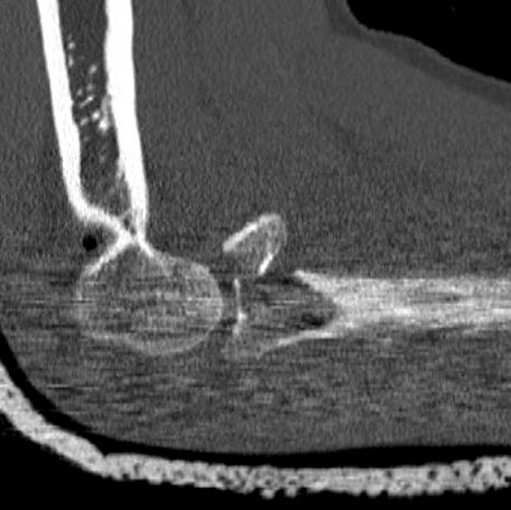

Figure 2: Same patient: preoperative CT scans, demonstrating the Mason Type III radial head fracture. No associated bony injuries could be detected.